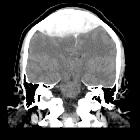

- <5% are located infratentorially in posterior fossa

In almost all cases, extradural hematomas are seen on CT scans of the brain. They are typically bi-convex (or lentiform) in shape, and most frequently beneath the squamous part of the temporal bone. EDHs are hyperdense, somewhat heterogeneous, and sharply demarcated. Depending on their size, secondary features of mass effect (e.g. midline shift, subfalcine herniation, uncal herniation) may be present.